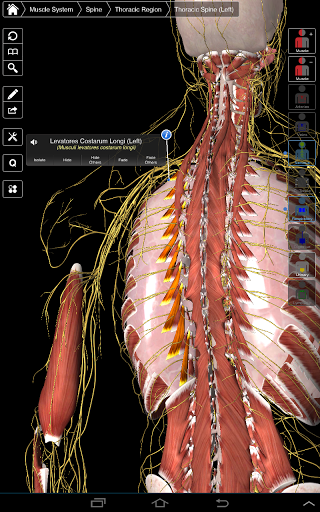

Essential Anatomy 3 représente la toute dernière technologie 3D révolutionnaire et un design innovant. Un moteur graphique 3D de pointe, construit sur mesure par 3D4Medical à partir de zéro, alimente un modèle anatomique très détaillé et fournit des graphiques de qualité exceptionnelle qu'aucun autre concurrent ne peut atteindre.

L'application représente une approche unique à l'apprentissage de l'anatomie générale. Les graphismes sont inégalés et rendent l'apprentissage, grâce à l'utilisation de contenu informatif et de fonctionnalités innovantes, une expérience riche et engageante.

⁃Muscles

⁃Nerfs

Essential Anatomy 3 est réactif, visuellement magnifique et sans effort. L'application est entièrement 3D, ce qui signifie que vous pouvez voir n'importe quelle structure anatomique dans l'isolement, ainsi que de n'importe quel angle.

La fonctionnalité intelligente trouvée dans l'application permet à l'utilisateur de dépouiller les couches de muscle via l'outil «scalpel». Cette application offre aux utilisateurs la possibilité d'activer / désactiver des systèmes sans avoir à désélectionner des structures individuelles ou à se frayer un chemin à travers une multitude d'onglets régionaux prédéfinis, comme d'autres applications.

---- Plus de 4000 structures anatomiques très détaillées

---- Nomenclature latine pour chaque structure anatomique